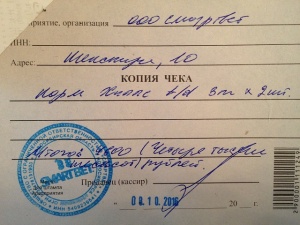

– вет диета Hills t/d для снятия налета с зубов, согласно листу назначений от 02.10.2016 (чек 1, копия чека 1) – 4600 руб.;

– вет диета Hills t/d для снятия налета с зубов, согласно листу назначений от 02.10.2016 (чек 1, копия чека 1) – 4600 руб.;